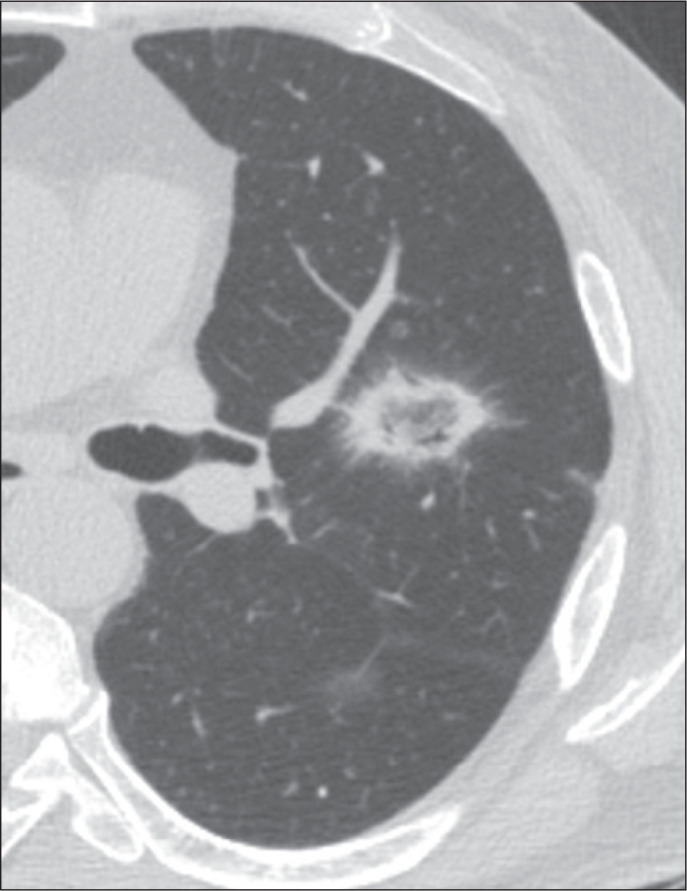

Objective: To characterize the main causes of the reversed halo sign (RHS) on computed tomography (CT) of the chest and its imaging features.

Materials and methods: This was a retrospective study reviewing all chest CT scans for which the report contained the term "reversed halo sign" among those performed between 2015 and 2020 at a tertiary care hospital.

Results: A total of 286 cases were identified, and the corresponding CT images and clinical data were reviewed. In this population, the most common cause of an RHS was pulmonary infarction (in 42%), followed by cryptogenic organizing pneumonia (in 17%) and bacterial pneumonia (in 16%). In addition, the CT characteristics of the RHS were identified in various conditions, such as pulmonary thromboembolism with pulmonary infarction, in which the RHS was typically smooth-walled and solitary with a peripheral distribution.

Conclusion: The RHS can be observed in many contexts, and its CT characteristics, in combination with the clinical picture, can help narrow the differential diagnosis.